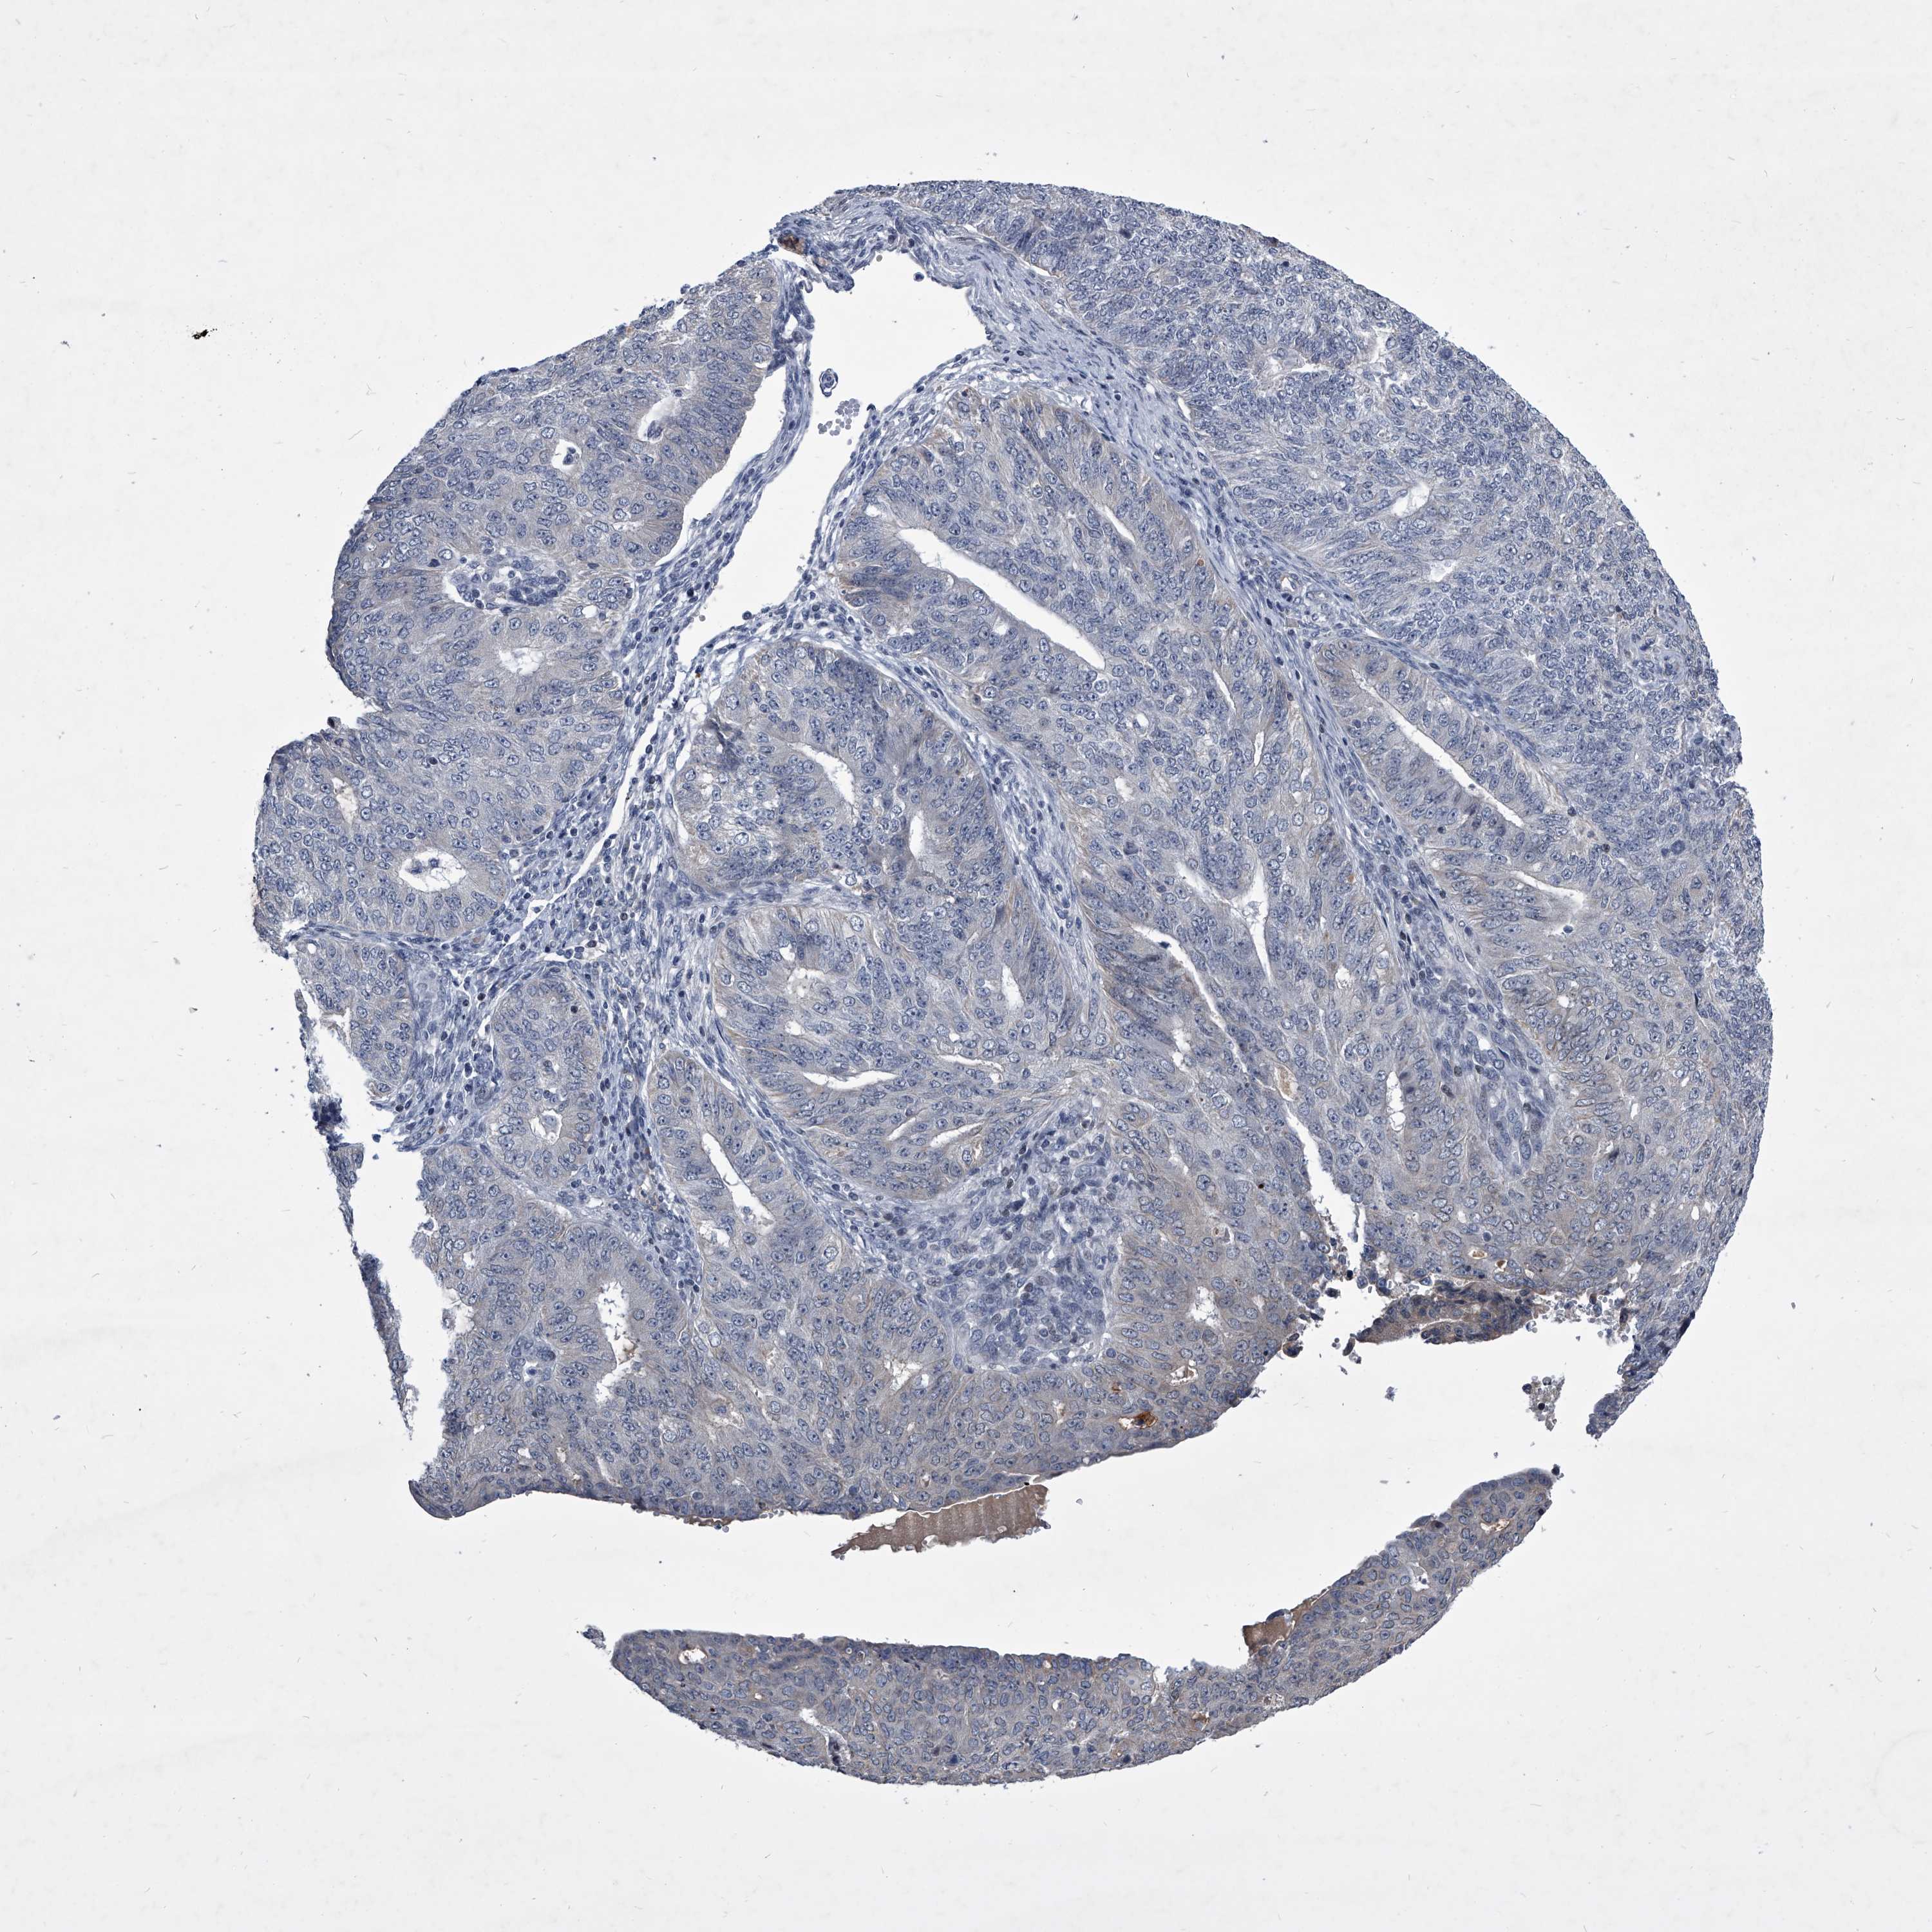

ENDOMETRIAL CANCER - Protein expressioni

A mouse-over function shows sample information and annotation data. Click on an image to view it in a full screen mode. Samples can be filtered based on level of antibody staining by selecting one or several of the following categories: high, medium, low and not detected. The assay and annotation is described here.

Note that samples used for immunohistochemistry by the Human Protein Atlas do not correspond to samples in the TCGA dataset.

Antibody stainingi

Antibody staining in the annotated cell types in the current human tissue is reported as not detected, low, medium, or high, based on conventional immunohistochemistry profiling in selected tissues. This score is based on the combination of the staining intensity and fraction of stained cells.

Each image is clickable and will lead to virtual microscopy that enables deeper exploration of all samples and also displays staining intensity scores, fraction scores and subcellular localization as well as patient and tissue information for each sample.

Antibody HPA030090

Antibody HPA030091

Staining

High

Medium

Low

Not detected

Intensity

Strong

Moderate

Weak

Negative

Quantity

>75%

75%-25%

<25%

None

Location

Nuclear

Cytoplasmic/membranous

Cytoplasmic/membranous,nuclear

Adenocarcinoma, NOS

Adenocarcinoma, metastatic, NOS